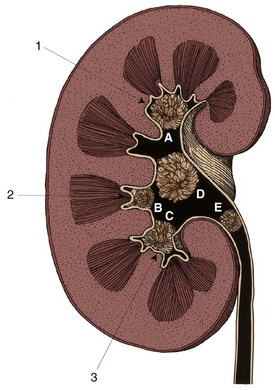

The walls of the calyces and the pelvis contain fibrous connective tissue and two layers of smooth muscle and are lined on their inner surfaces by transitional epithelium (Dixon and Gosling, 1982) (Figs. 53-1 and 53-2). Thin muscle layers originate in the minor calyces and form a spiral, helical arrangement (Fig. 53–3).

Figure 53–1 Low-magnification view of a section through the kidney. The renal medulla ends in the pointed renal papilla. Urine empties into the Y-shaped space made up of the renal calyces (the arms of the Y) and the pelvis (the base of the Y).

The ureter demonstrates two continuous thin muscle layers with a loosely spiraled internal layer and a more tightly spiraled external layer. In the lower third of the ureter, a third outer longitudinal layer is present. All three layers merge with the three layers (inner longitudinal, middle circular, and outer longitudinal) of the bladder wall, which run longitudinally, transversely, and obliquely. Beneath the outer muscle coat is the serosa, made up of loose connective tissue and containing blood vessels and lymphatics (Hanna et al, 1976; Notley, 1978) (Figs. 53-4 and 53-5).